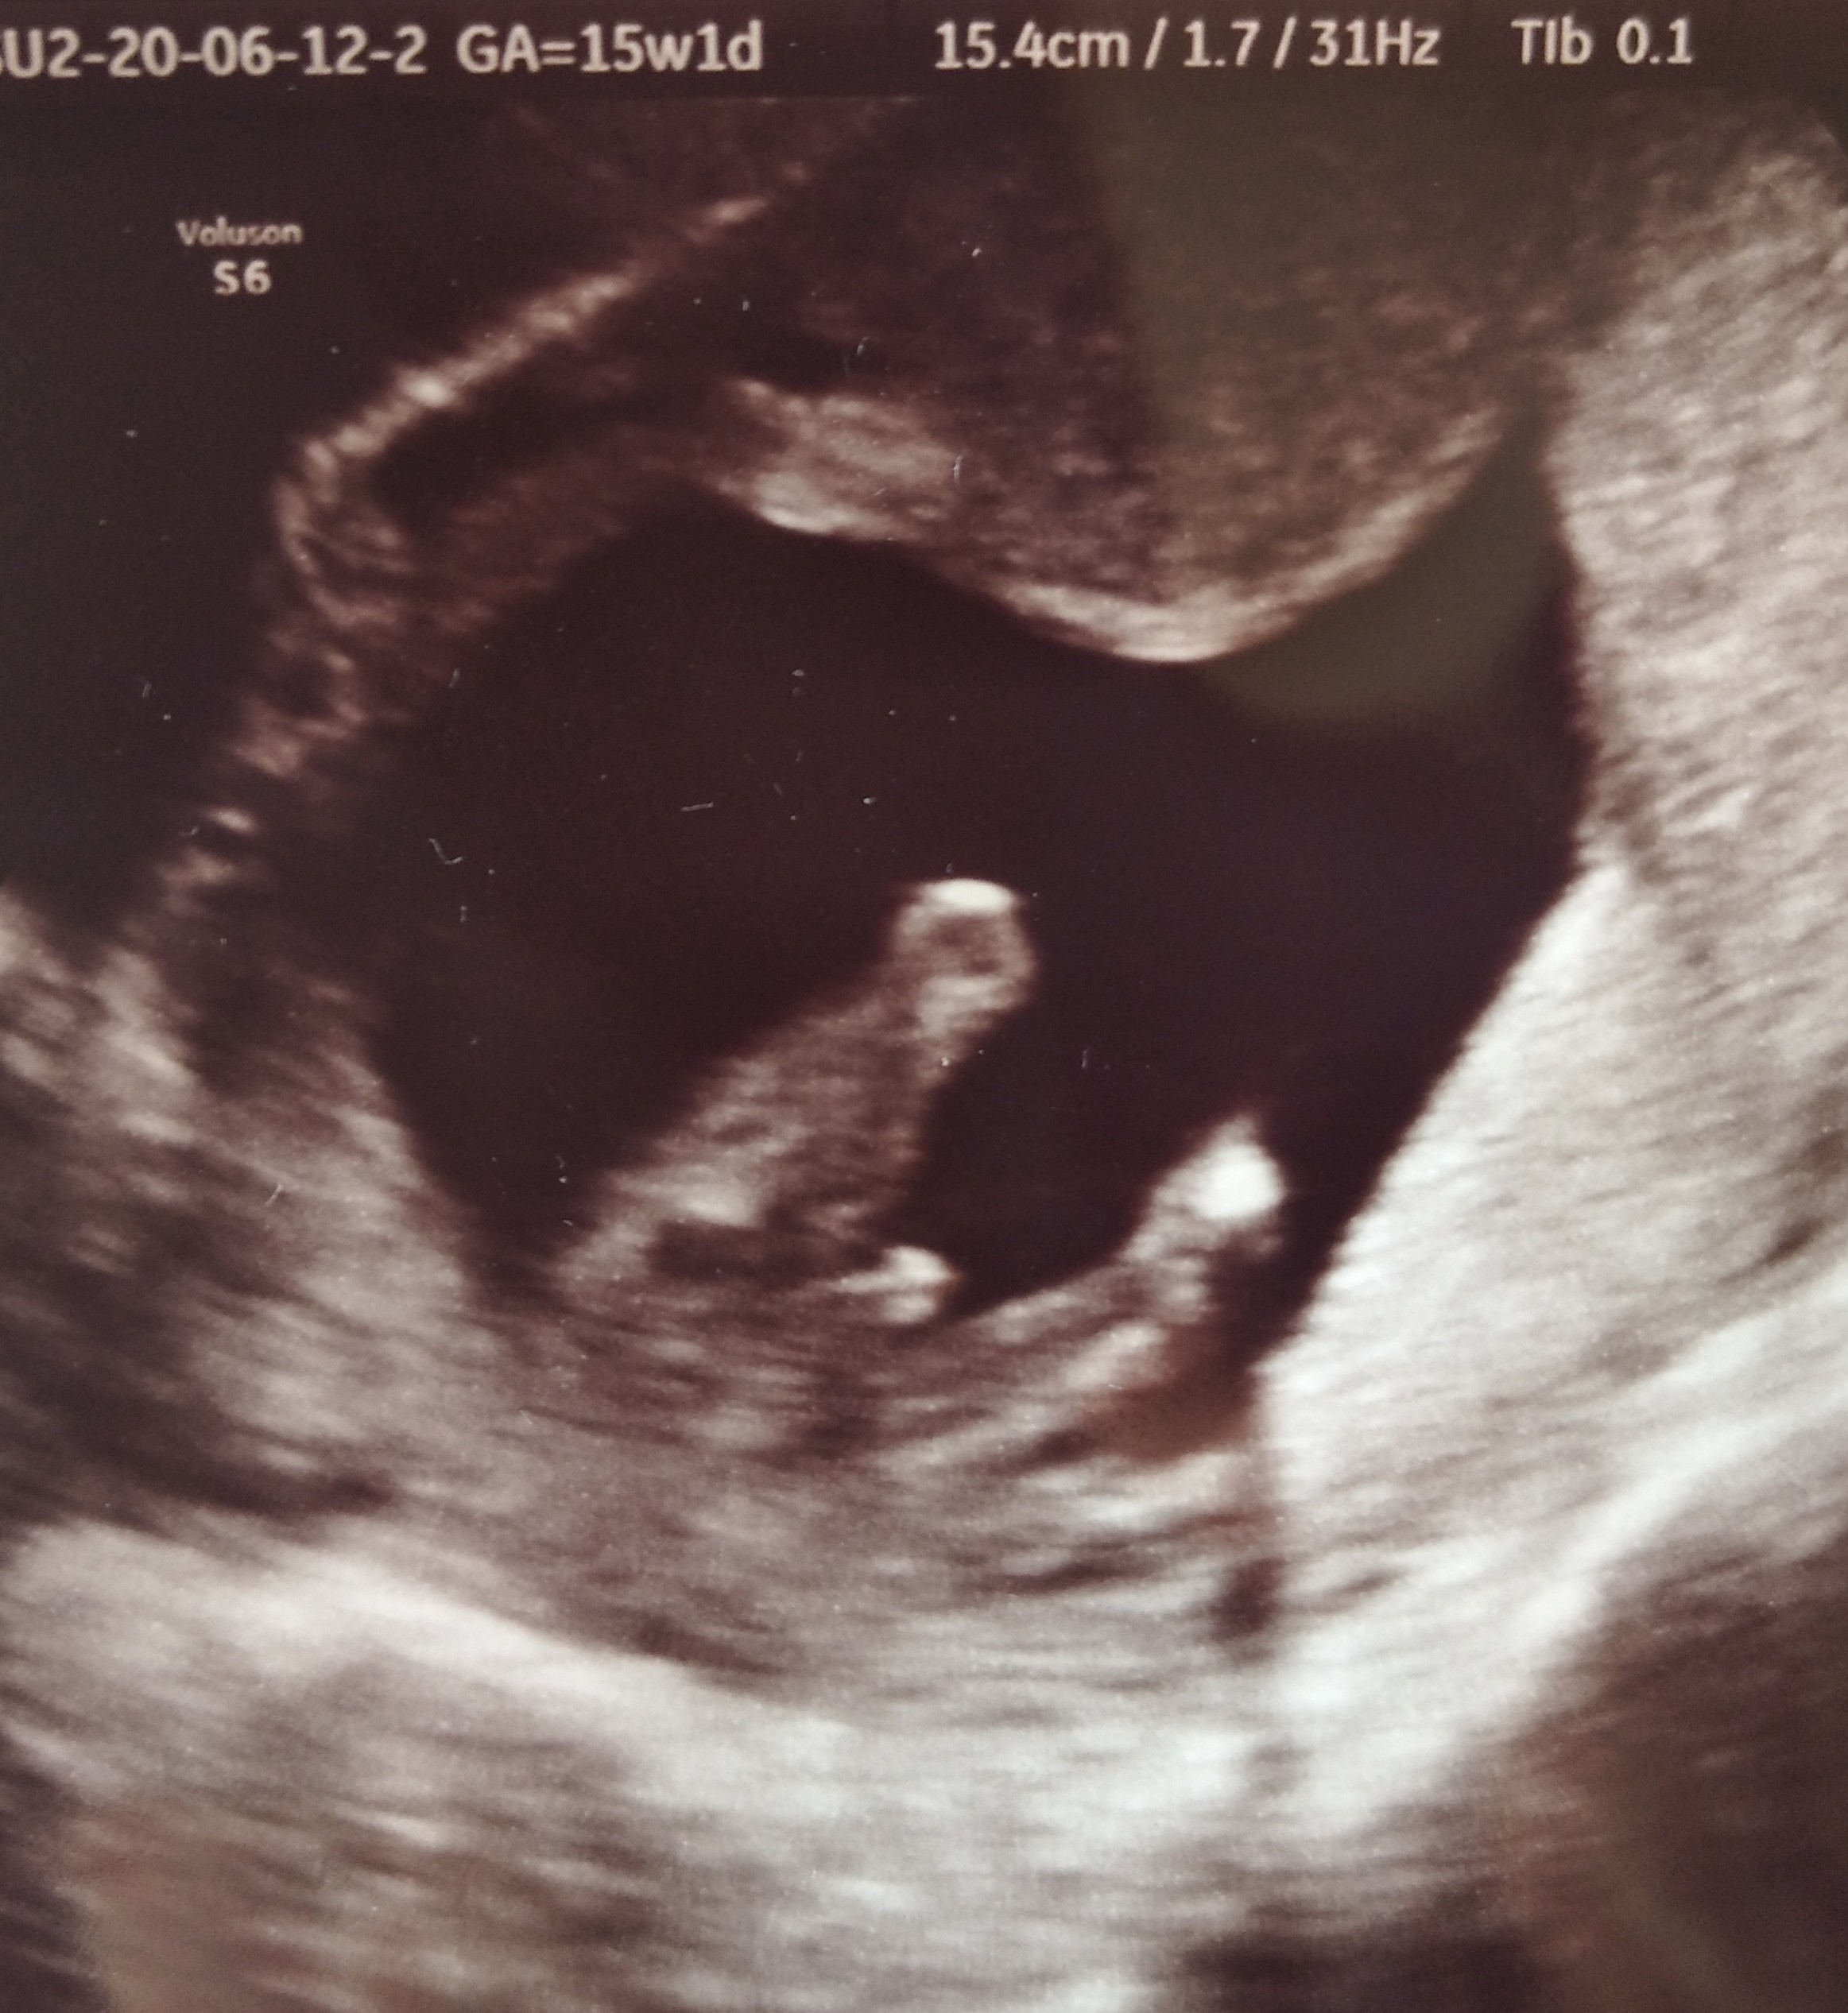

Mnie tez bolał brzuch bo dzidzia nie chciała współpracować i pani musiała się namęczyć z 40 min żeby wszystko zmierzyć... myśle ze tak może być, jutro już powinno być okej! Ja czułam w dzień badania (ale miałam rano) i następnegoMam pytanie do dziewczyn które bolał brzuch/podbrzusze po USG, przed wczoraj byłam na USG prenatalnym, mam sporo tłuszczyku i lekarz delikatnie mówiąc dość mocno jeździł mi ta głowica. Wczoraj bolało mnie podbrzusze ale przyjęłam to ze spokojem ale dzisiaj wydaje mi się to już ciut za długo. Co o tym sądzicie? Jeśli jutro mi nie przejdzie to chyba poproszę moją gin o wizytę. Jak długo bolał was brzuch po USG?